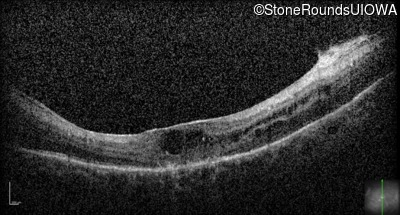

Optical Coherence Tomography - Left - Hand Motion

Exemplar / OCT Stack

OCT Stack